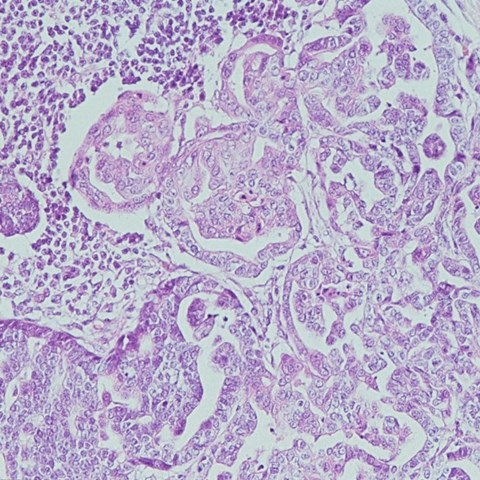

Bild: Cancerceller i en metastas från juvertumör till lymfknuta. Foto Eva Hellmén